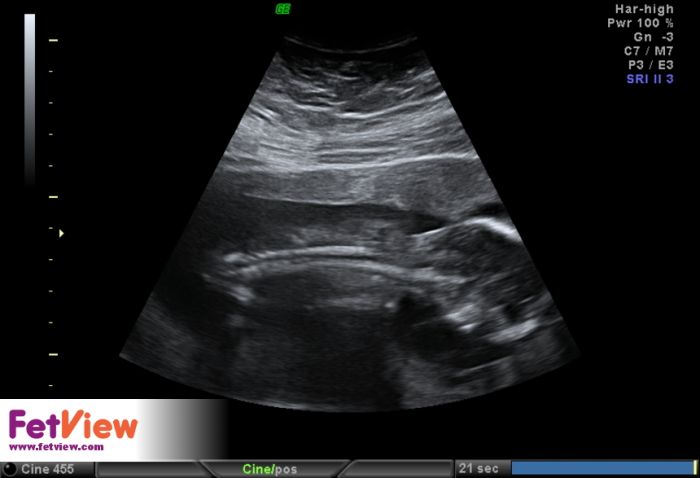

Ahojky, tak sse hlásím po kontrolách, včera jsme byla u svého doktora a vše ok, jen maličká nechtěla moc spolupracovat pořád na nás vystrkovala záda asi se styděla :-) takže zkontroloval co se dalo, chtěl udělat i foto 3d ale nebylo fakt nic vydět :-( takže snad příště, máme skoro 11cm .-) fotečky přikládám. U genetičk taky vše v pořádku i ostatní výsledky po odběru klků ok, tak se mi ulevilo. No a dneska jsme byla u Apolináře na kontrole po tom odběru, udělali mi podrobný ultrazvuk a tak jsme viděla všechno - hlavu, oči, žaludek, pusu, ruce i s kostičkama, močový měchýř...tý jo koukla jsme jak divá :-) doktor byl super všechno mi vysvětlil a popsal a moc hezky jsme si i popovídali :-)

Tak se hlásím z kontroly na genetice a podrobný ultrazvuk vše vypadá v pořádku. Po odběru choriovych klku jse vše v pohodě. Žádný problém tam není. Miminko v pořádku i ten tok pupečníku je lepší po těch tabletkach. Tak jsem šťastná jen se nechtěla nechat vyfotit celá. Tak jen z prifilu